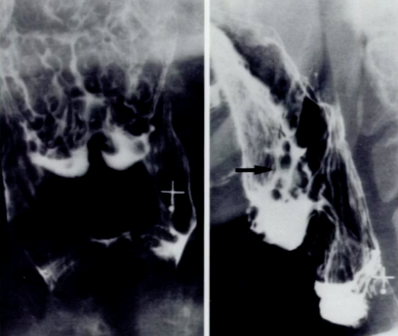

What could be causing the asymmetry seen on the right side of the image shown below?

It is a slight filling defect, it could be an early carcinoma.

What could be causing the sign shown below?

An advanced carcinoma. Note the multiple filling defects with ulcerations.